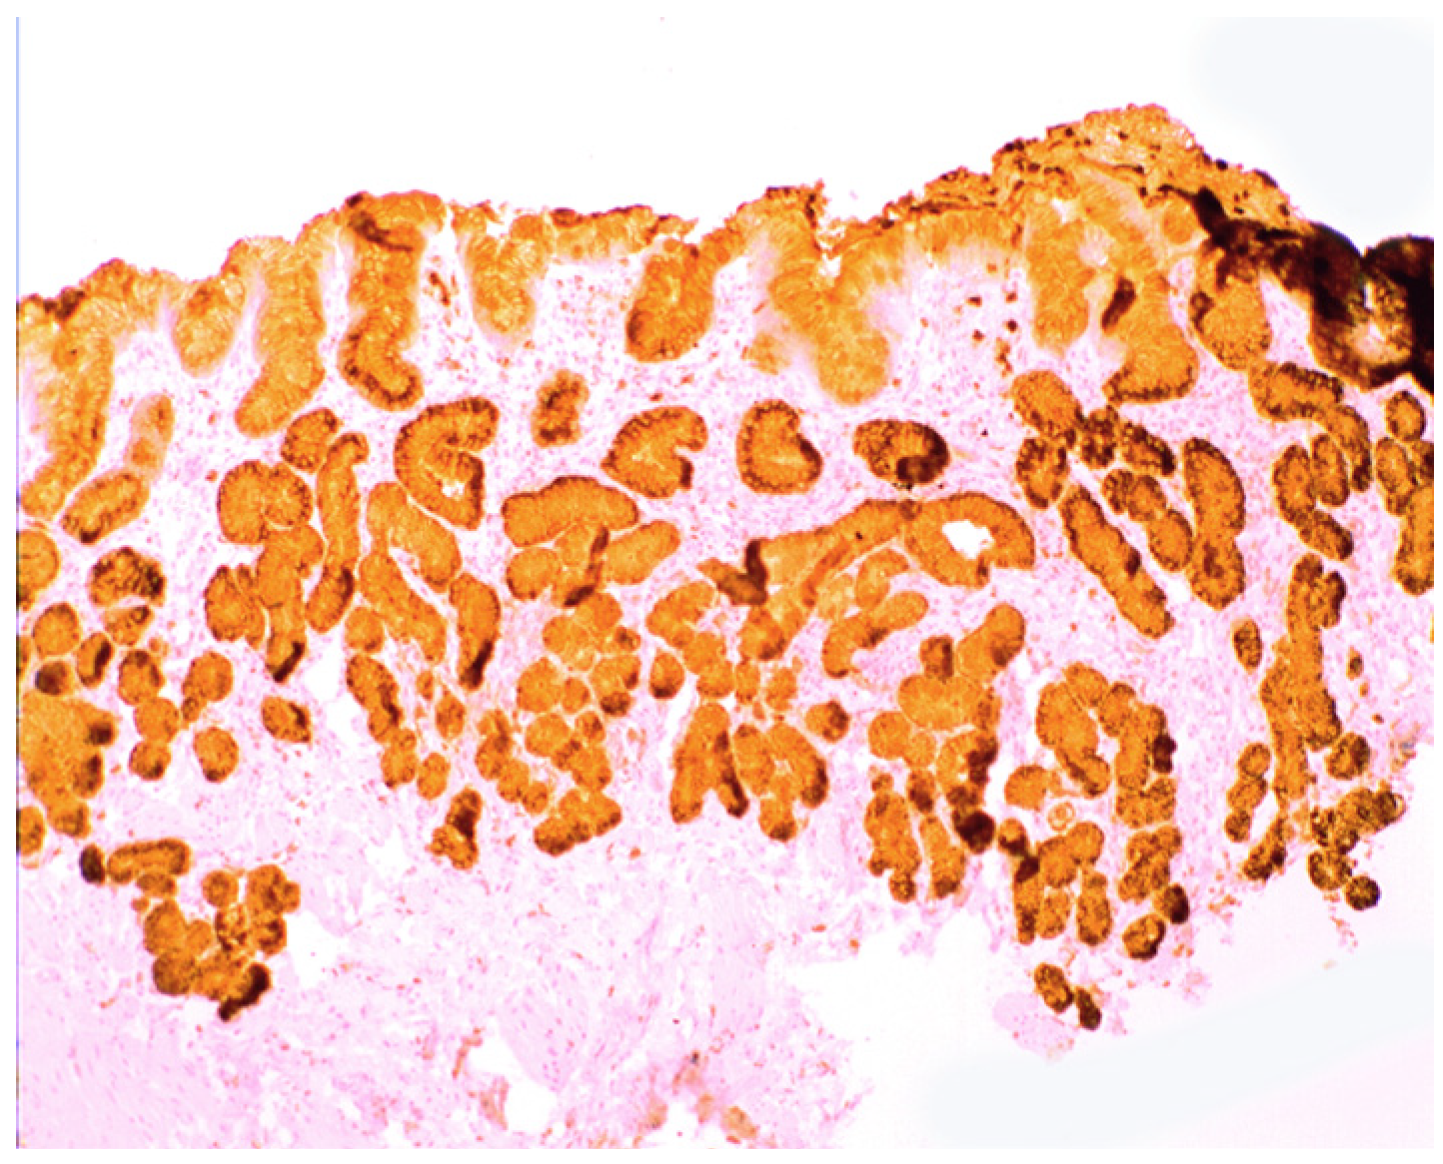

Increased lysozyme immunoreactivity was found In Barrett’s oesophagus; in the surface columnar epithelium, in the columnar epithelium of the pits of the glands (Figure 1), in goblet cells (Figure 2), as well as in Paneth cells in cases with intestinal metaplasia [24].

Barrett’s mucosa (pyloric phenotype) showing lysozyme expression in surface epithelium, foveolar epithelium, and pyloric glands (lysozyme immunostain, ×4).